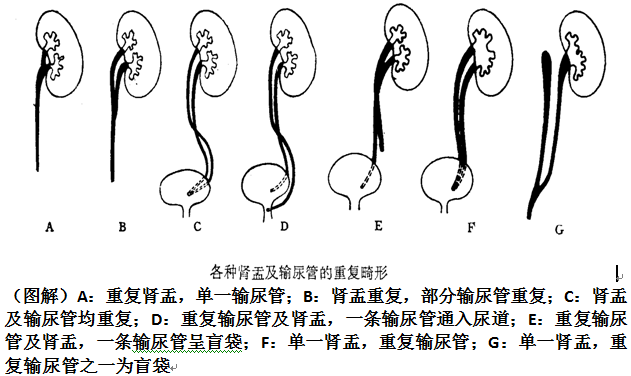

肾盂输尿管重复畸形

胚胎早期有两个输尿管芽进入一个后肾胚基所致。

一个肾脏分为上、下两部,各有一套肾盂和输尿管。上、下两部多不相等,上部肾盂往往细小,发育不全,下肾盂较大。

尿路造影是诊断肾盂输尿管重复畸形的首选方法